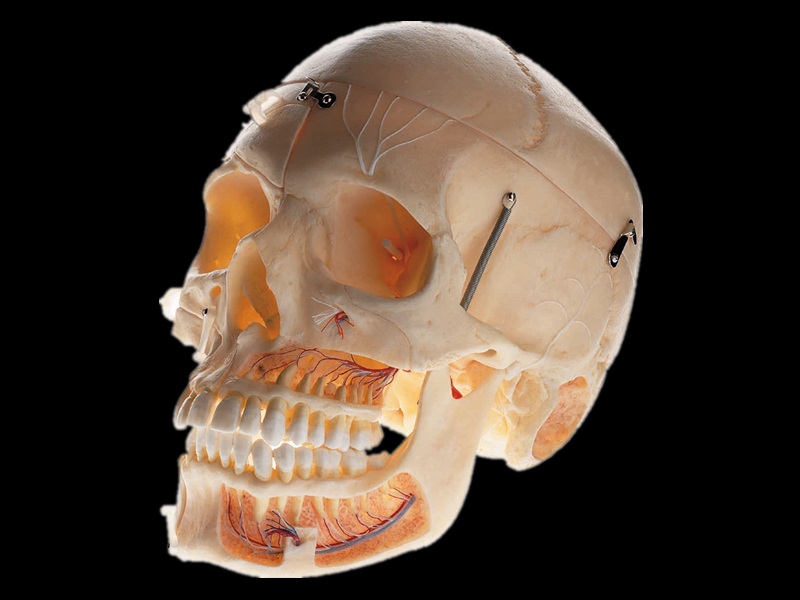

Анатомия детского черепа: Рентгеновские снимки и описание